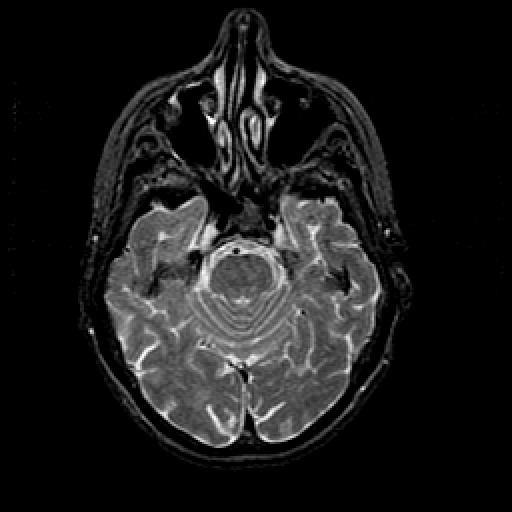

T2-weighted structural MR: Slice 17

Slice 17